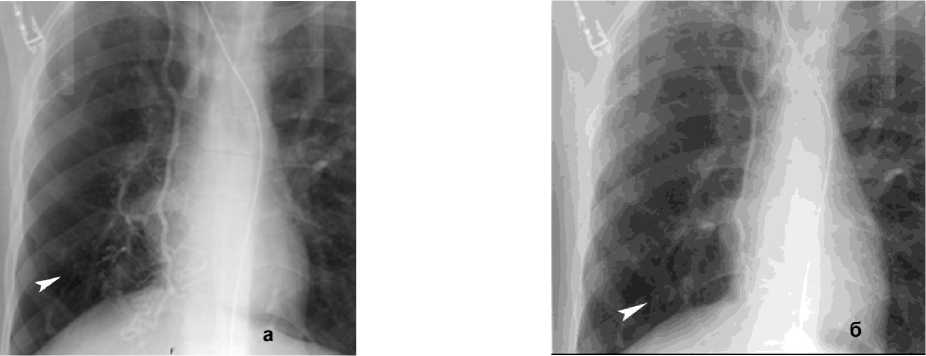

Преимущественно это были пациенты, имевшие ЛК 1А – 103 (69,25%) случая – с разнообразной патологией (табл. 1), ЛК 1Б – 20 (13,6%), ЛК 1В – 2 (1,3%). В этой группе превалировала бронхоэктатическая болезнь, ТБЦ в анамнезе, рак лёгких, саркоидоз, инфекционные поражения лёгких, эхинококк (рис. 3). Причиной ЛК 2А послужили у 14 (9,3%) пациентов рак лёгкого, пневмонии после Сovid-инфекции (рис. 4, а), включая и поражение бронхов, язвенный бронхит, состояние после АКШ, опухоль средостения (рис. 6), ЛК неясной этиологии, ЛК 3А и ЛК 3Б соответственно составляли 3 (2,1%) и 2 (1,3%) случая, причиной были бронхоэктатическая болезнь, в анамнезе перенесённые ТБЦ, аорто-бронхиальное соустье (табл. 1).

Рисунок 4. КТ грудной клетки с болюсным КУ (артериальная фаза), аксиальные срезы: а (лёгочный режим) – геморрагическое пропитывание в средней доле правого лёгкого (стрелка); б (средостенный режим) – расширение и извитость бронхиальных артерий (сосудистая мальформация – стрелка)

Figure 4. Chest CT with bolus contrast enhancement (arterial phase), axial slices: a (lung window) – hemorrhagic infiltration in the middle lobe of the right lung (arrow); б (mediastinal window) – dilation and tortuosity of bronchial arteries (vascular malformation – arrow)

При КТ-исследовании косвенным признаком состоявшегося ЛК является геморрагическое пропитывание лёгочной ткани в виде зоны неоднородного повышения плотности от «матового стекла» до мягкотканных значений с визуализаций просвета бронхов (рис. 4, а). Локализация пропитывания в большинстве случаев позволяет установить бассейн повреждённого сосуда. КТ-признаком продолжающего кровотечения является эктравазация контрастного препарата в виде гиперденсивных участков неправильной формы, появляющихся в артериальную фазу (при артериальном кровотечении) и увеличивающихся по размеру в последующие фазы КУ. КТ позволяет выявить не только признаки кровоизлияния, но и в большинстве случаев причину его возникновения (рис. 4, б).